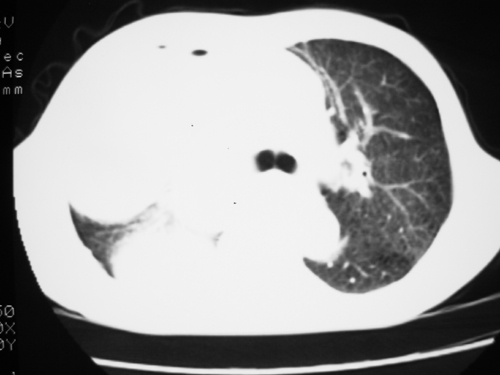

以下是引用yangyudong333在2008-4-29 5:46:00的发言:[br]1左上叶结节呈分叶状,边缘毛刺,考虑肺癌并纵隔淋巴结转移可能性大,结核待排,[br] [br]2右侧多发包裹性胸腔积液

以下是引用zsl6918在2008-4-29 9:15:00的发言:[br]右侧包裹性积液穿刺术后改变,肺内多发结节不除外转移可能。建议查胸水,问病史。